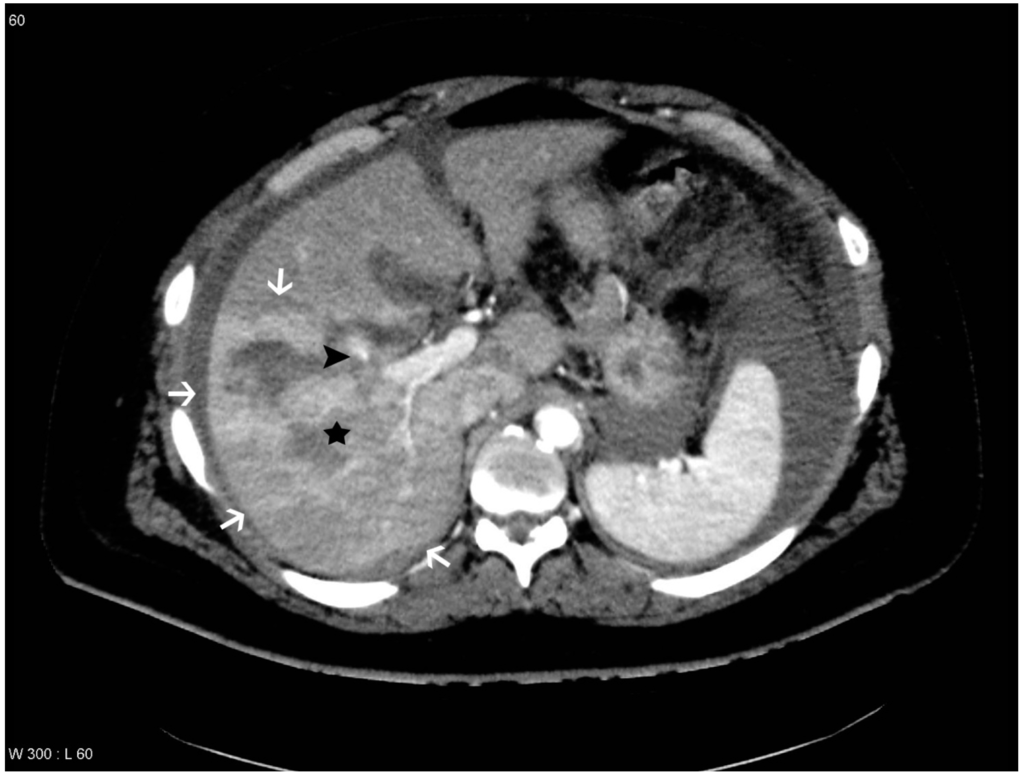

Figure 3. Patient with liver lesion in segment 5, 6, 7 and 8. THAD is seen in the periphery of the lesion and pseudoaneurysm and arteriovenous fistula (PS/AF) is not present according to the gold standard. However, one observer suspected a pseudoaneurysm, which is marked with a black arrowhead. The liver lesion is marked with a black star and the areas with THAD are marked with white arrows.

THAD was defined as an increased arterial enhancement in relation to the liver lesion without resemblance of PS/AF. THAD after liver trauma has previously been described as a localized arterial enhancement with a polymorphous appearance [16,18]. The senior radiologist did not comment on THAD in the initial reading, primarily because THAD is regarded as a benign phenomenon. Therefore, presence of THAD was defined by a consensus between at least two out of three observers (residents in radiology) (Figure 1, Figure 2, Figure 3 and Figure 4).

The observers diagnosed PS/AF on the follow-up CT scan with an averaged sensitivity of 69.7% and specificity of 96.5% when compared to the gold standard. However, different sensitivities and specificities were found if THAD was included as a variable. If THAD was absent on the follow-up CT scan the averaged sensitivity and specificity were 85.7% and 98.0%, while the averaged sensitivity and specificity decreased to 65.5% and 95.0% if THAD was present (Table 1). This indicates that THAD on the follow-up CT scan can result in both false positive and false negative observations when looking for PS/AF after blunt liver trauma (Figure 3 and Figure 4). Furthermore, it was shown that THAD in this study had a significant influence on the diagnosis of PS/AF for the three residents, as the likelihood of agreement for evaluation of PS/AF between the observers and the gold standard was 89% when THAD was present, and 98% when THAD was absent (p = 0.04).

PS/AF can be recognized and distinguished from THAD by the location, the appearance, and the HU level. PS/AFs seen in 14% of the patients were all oval or round except one, which was linear, and all had focal enhancement with mean HU levels of 170. All PS/AFs were found within the liver lesions (Figure 1 and Figure 4). PS and AF were indistinguishable as stated previously by others [9]. Areas with THAD seen in 54% of the patients had hazy borders, were all found in the periphery of the lesion and with mean HU levels of 100 (Figure 1, Figure 2, Figure 3 and Figure 4).